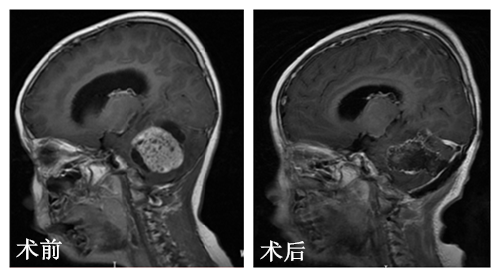

为明确诊断,李家夫妇带着女儿来到广州求治,广东三九脑科医院小儿神经外科进行MR平扫及增强,提示后颅窝占变,以右侧小脑半球为主,且瘤脑界面清晰。

小儿神经外科杨宝应主任及其团队进行术前讨论,彤彤的手术指征明确,无手术禁忌症。在完善术前准备之后,由杨宝应主任主刀,予显微镜下为彤彤施行了右小脑占位性病变切除术,成功把彤彤脑袋里大小约2*2.5cm的灰白色肿瘤组织切除下来。术后一天,彤彤恢复意识,无发烧感染,头部四肢活动良好,于是辅以放射治疗。术后病理结果:髓母细胞瘤。